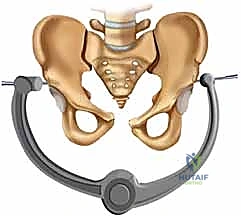

| طريقة العلاج | الراحة التامة في السرير لأسابيع، استخدام حزام الحوض (Pelvic Binder)، مسكنات الألم. | تدخل جراحي لرد العظام وتثبيتها ميكانيكياً باستخدام صفائح ومسامير معدنية. |

يتم تقييم المريض بشكل شامل (أشعة سينية، أشعة مقطعية ثلاثية الأبعاد) لتحديد حجم الإصابة بدقة. تُجرى العملية تحت التخدير العام لضمان استرخاء العضلات بالكامل وعدم شعور المريض بأي ألم. يتم وضع المريض على ظهره على طاولة العمليات، وتُعقم منطقة البطن والحوض بالكامل.